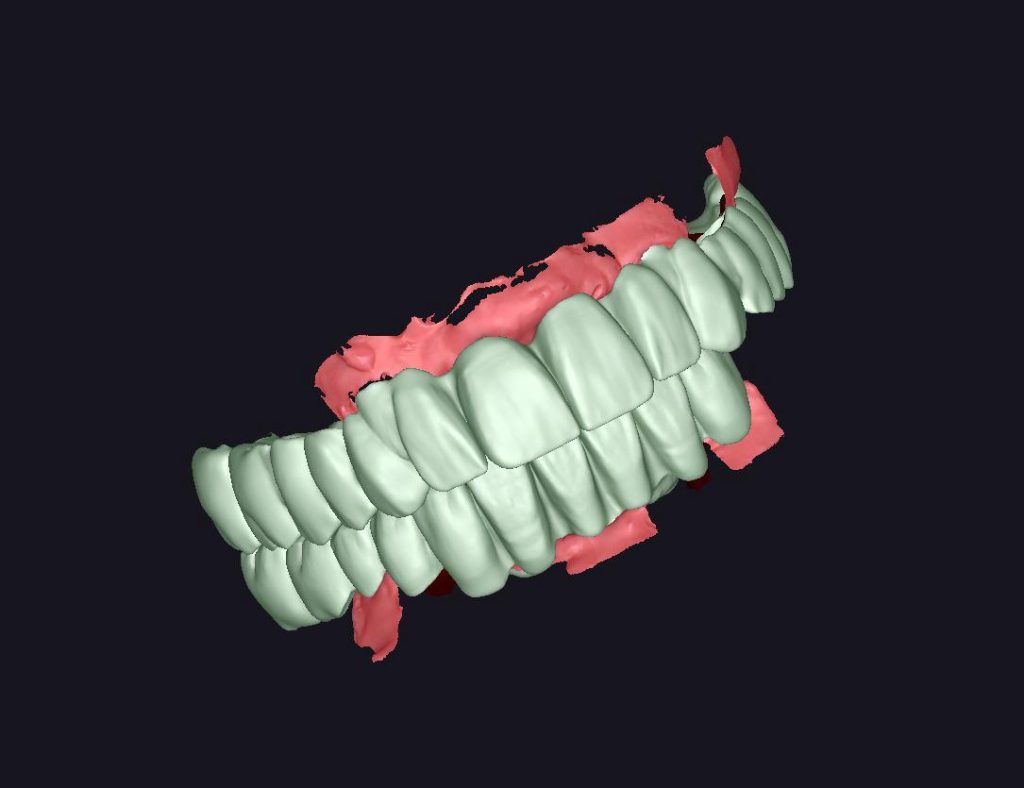

MONOLITIK ZiRKONYUM INLEY ONLEY

MULTILAYER ZiRKONYUM INLEY ONLEY

MONOLITIK IMPLANT USTU ZIRKONYUM & ÜSTTEN ViDALI ZİRKONiUM

MULTILAYER IMPLANT ÜSTÜ ZIRKONYUM & ÜSTTEN VİDALI ZIRKONYUM